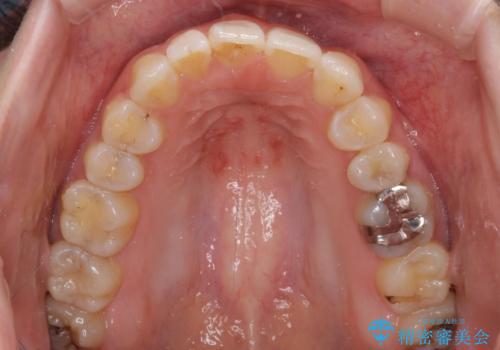

- 矯正治療の後戻りが気になるとのことで来院された患者様です。

上顎の後戻りをインビザライン・ライトで治療することとしました。

上顎のみの治療を希望されたため、咬み合わせをしっかりと改善することはできませんでしたが、審美面が大きく改善され、日常生活の機能面でも不具合を感じることはなく、大変満足していただきました。